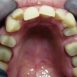

Interdisciplinary Treatment of Patients with Deep Overbite and Parafunctional Activity

Bruxism is defined as parafunctional grinding of teeth and due to the excessive wear of the posterior teeth, patients with long-standing bruxism often have pathological deep overbite. For many decades, treatment of bruxism and deep overbite was focused on reshaping the bite for achieving an occlusion free of deviations. Despite large efforts, the management of bruxism and subsequent deepening overbite was not obtained.